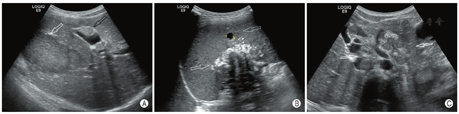

病例2,男,12岁1个月,因间歇性腹痛5个月余,在外院就诊时发现腹部包块来院。超声检查发现后腹膜、肝脏、胆囊壁、脾脏、膈肌等组织器官多发低回声包块,形态不规则,包块内可见多发沙砾样钙化斑(图2A, B),最大包块位于腹腔,长径16.0 cm;较小包块呈类椭圆形,较大包块呈分叶状,后腹膜部分包块互相融合包绕腹部大血管(图2C),包块内部血供丰富,较大包块可见液化区。行手术活检,术后病理诊断促结缔组织增生性小圆细胞肿瘤,基因检测显示EWSR1(22q12)基因断裂。活检后开始规律化疗,超声每隔1个月定期随访。化疗期间病灶增大、病变进展,发病1年2个月后患儿死亡。